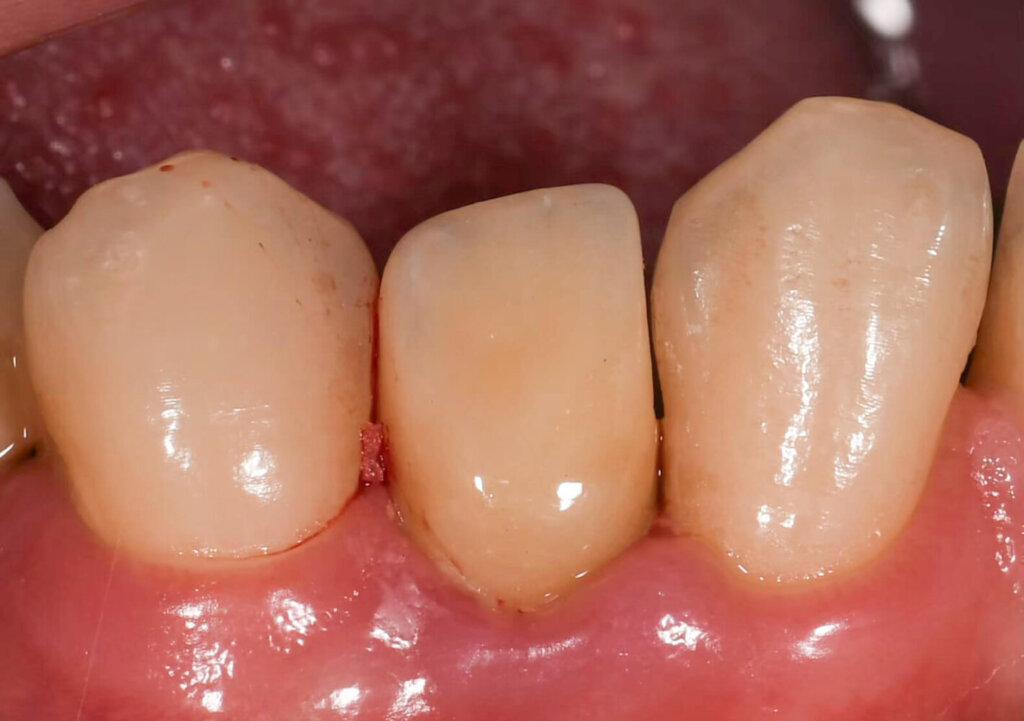

精準定位植牙,瞬間擺脫缺牙困擾

Before

After

A先生

A 先生的下排牙齒先天少一顆牙,導致周邊牙齒通通內擠過來,但仍然有一個小縫,而A先生一直以來的願望,就是能將這個縫補好。

雖然看起來是一個縫,但裡面的空間其實很小,因為除了上面牙齒傾倒,還要考量內部的骨頭空間,因此不是單純肉眼說可以就可以的。

A先生前後在其他間診所評估後,但因為空間狹小提升植牙難度,被拒絕了好幾次。

來到京鼎牙醫診所諮詢後,發現有X-Guide藍光導航機,且林建佑院長相當重視精准度,一顆植牙也會使用導航,提高成功率、讓患者用得長久!

後來手術前先用斷層確認骨頭狀態,來X-Guide藍光導航機來輔助植牙,有GPS定位找出適合的角度植牙,就算是小空間也能提升精准度,也減少患者要搭配其他療程的痛苦。

由於先天缺牙使用越久、年紀越大,對於咬合影響更劇烈,因此不論是後天缺牙還是先天少牙都會影響,因此先天缺牙也建議好好看待。